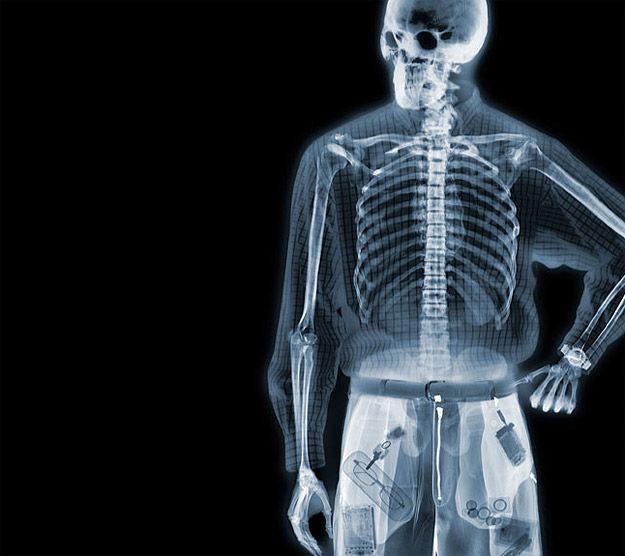

Благодаря дальнейшим исследованиям рентгеновских лучей (Чарльз Баркл: измерения рассеянных лучей с использованием способности лучей Рентгена разряжать наэлектризованные тела (Нобелевская премия 1917 г.), Лауэ: дифракция рентгеновских лучей (Нобелевская премия 1914 г.), отец и сын Брэгги: точное определение расстояния между атомами в кристаллах с помощью рентгеновских лучей (Нобелевская премия 1915 г.)), в физику пришли два фундаментальных научных факта: рентгеновские лучи обладают такими же волновыми свойствами, как и световые лучи; с помощью рентгеновских лучей можно исследовать не только внутреннее строение человеческого тела, но и заглянуть вглубь кристаллов.

По рентгеновским снимкам ученые теперь могли легко отличить кристаллы от аморфных тел, выявить сдвиги цепочек атомов в глубине непрозрачных для света металлов и полупроводников, определить, какие изменения в структуре кристаллов происходят при сильном нагревании и глубоком охлаждении, при сжатии и растяжении.